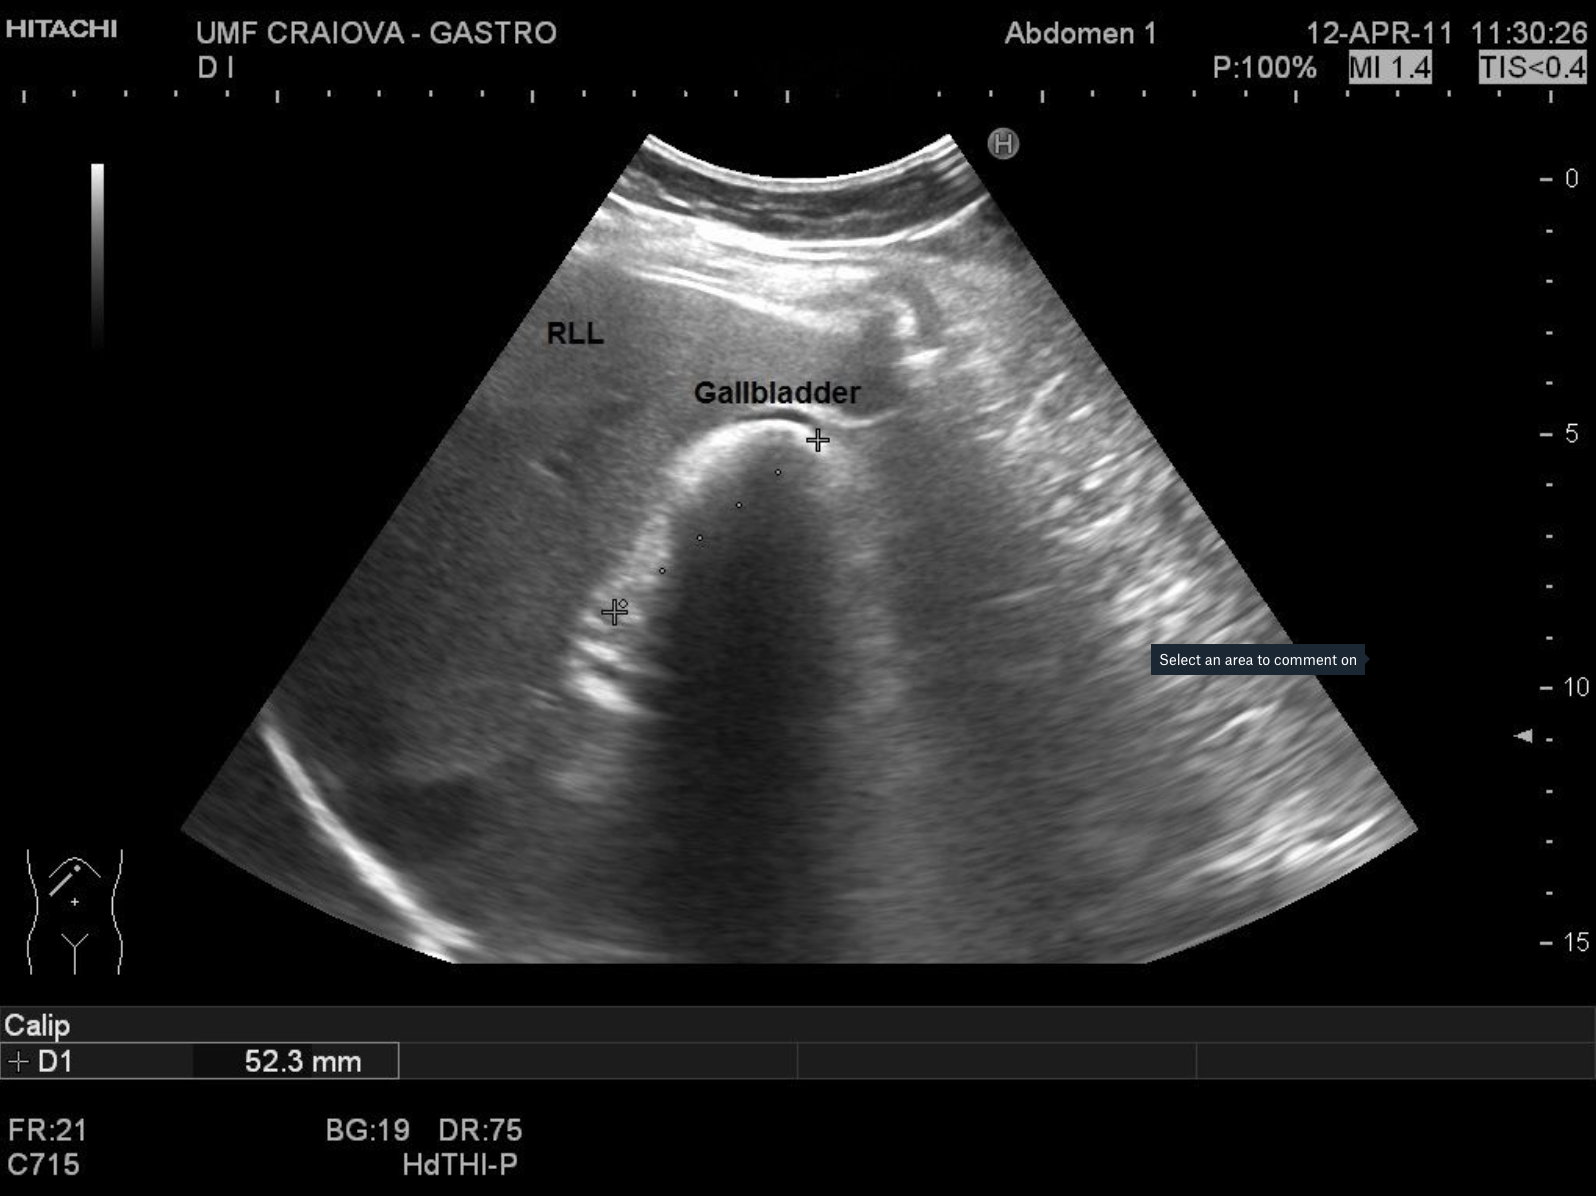

Gallstones [1 image] Categories BASIC ULTRASOUND IMAGESGallbladder and Bile DuctsGallstones and Sludge in Gallbladder TITLE: Gallstones DESCRIPTION: 40 year old male, gallstone in a scleroatrophic gallbladder EMAIL CONTACT:constantinescu.codruta@yahoo.com KEYWORDS:gallbladder, gallstones, gallbladder ultrasound Related postsJanuary 5, 2021Walled-off pancreatic necrosis [2 images]Read more